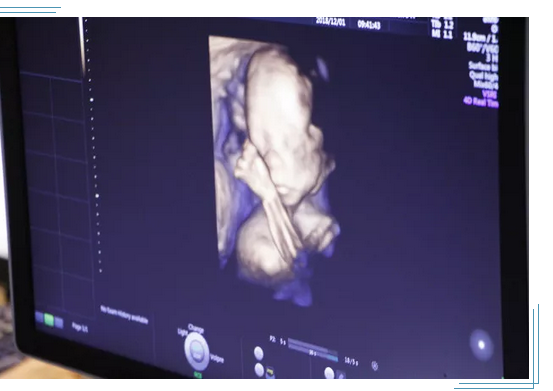

四维彩超在当代已经可以实现立体、实时观察胎儿活动图像。在孕期,四维彩超可以帮助孕妇排查胎儿是否有畸形。那么,这样的彩超和传统的B超相比,价格自然也会相对高一些。通常在300—400元之间,但是每个地区和医院的价格都有所差异,具体还要按照当地的医院而定。

2、4D超声可多方位、多角度地观察宫内胎儿的生长发育情况,为早期诊断胎儿先天性体表畸形提供准确的科学依据,可以实时清晰地观察宝宝动态运动。它不存在射线、光波和电磁波等方面的辐射,高分辨率容积成像(HD Live)、容积SRI (V SRI),新一代的4D 渲染模式,图像质量卓越。